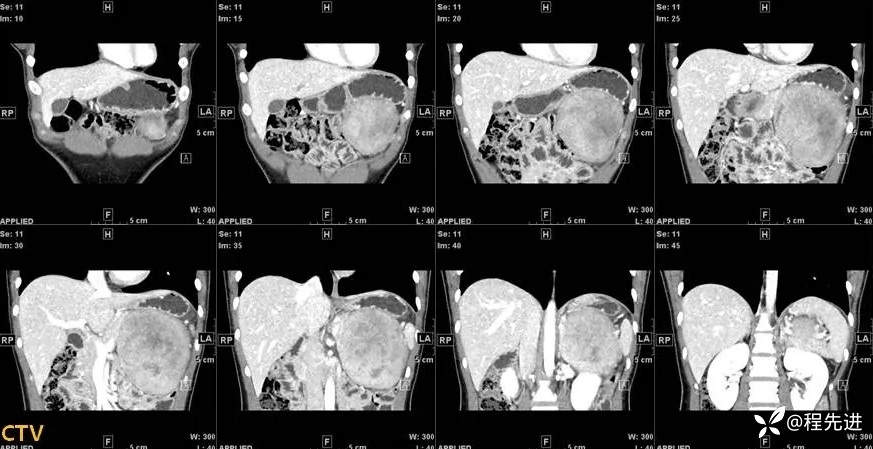

【现病史及既往史】:患者4天前于外院行CT检查发现胰腺肿物,胰胃间隙见一肿物,大小约108mmx103mmx122mm,考虑胰腺实性假乳头状瘤可能性大,无伴发热、畏寒,无恶心、反酸,无呕血、黑便。患者起病以来,一般情况可,无头晕、头痛,无心悸、气促,无腹泻、便秘,无排陶土样大便。精神可,胃纳、睡眠差,尿量如常,尿色淡黄,大便规律,体重未见明显改变。

影像检查: